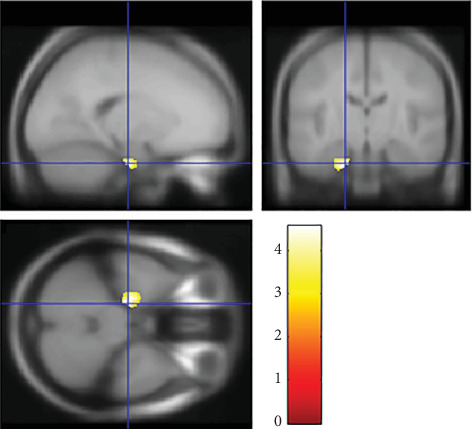

Previous research by Mehrinejad et al. found that parenting style affects offspring's brain development which later determines their creativity. They show that there is a significant positive relationship between authoritative parenting style and creativity. Meanwhile, neuroimaging studies by Takeuchi et al. have explained that offspring's creativity also differs depending on their empathizing-systemizing cognitive style. They show that both EQ and SQ were significantly and positively correlated with creativity. Combining the previous studies, we hypothesize that there exists an effect of the positive interaction between parenting style and the offspring's E-S cognitive style on the offspring's brain development and creativity. Whereas previous research on the offspring's creativity has focused on one dimension only, in the current study, for the first time, we investigated the effect of the interaction between parenting style and the offspring's E-S cognitive style on the offspring's brain development and creativity. We used voxel-based morphometry and questionnaires to investigate the gray matter correlates of the interaction between parenting style and the offspring's E-S cognitive style. With 675 healthy participants (average: 20 years old), using cross-sectional whole-brain multiple regression, we found significant interactive effects between parenting style and offspring's E-S cognitive style on regional gray matter volume (rGMV) in the right supramarginal gyrus (R-SMG). We also found that the rGMV in the R-SMG was significantly and positively correlated with the offspring's originality/fluency scores, a dimension of creativity. Our findings suggest that offsprings who are raised with the appropriate parenting style according to their E-S cognitive style have a larger rGMV in the R-SMG. These offsprings exhibit a higher level of creativity, especially originality in divergent thinking, the ability to generate an idea that is different from that of others. In the future, we hope this research can provide critical information for parents regarding the parenting style that suits their offspring's E-S cognitive style to improve offspring's creativity and quality of life.